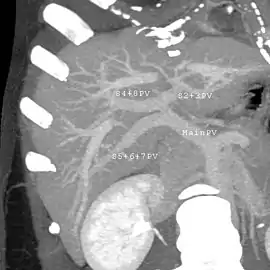

With the recent advances of noninvasive imaging, living liver donors usually have to undergo imaging examinations for liver anatomy to decide if the anatomy is feasible for donation. The evaluation is usually performed by multidetector row computed tomography (MDCT) and magnetic resonance imaging (MRI). MDCT is good in vascular anatomy and volumetry. MRI is used for biliary tree anatomy. Donors with very unusual vascular anatomy, which makes them unsuitable for donation, could be screened out to avoid unnecessary operations.

MDCT image. Arterial anatomy contraindicated for liver donation

MDCT image. Portal venous anatomy contraindicated for liver donation